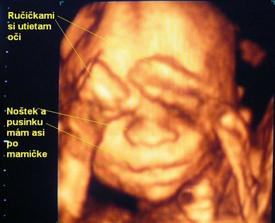

V januari sme sa dozvedeli, ze sa nasa rodinka rozrastie. 🙂 Bola to ta najkrajsia sprava. Tehotenstvo nam ubehlo ako voda a teraz uz kazdu chvilu netrpezlivo cakame prichod babatka. Uzivam si posledne chvilky s bruskom a ako kratim si cas, to tu mozete vidiet...